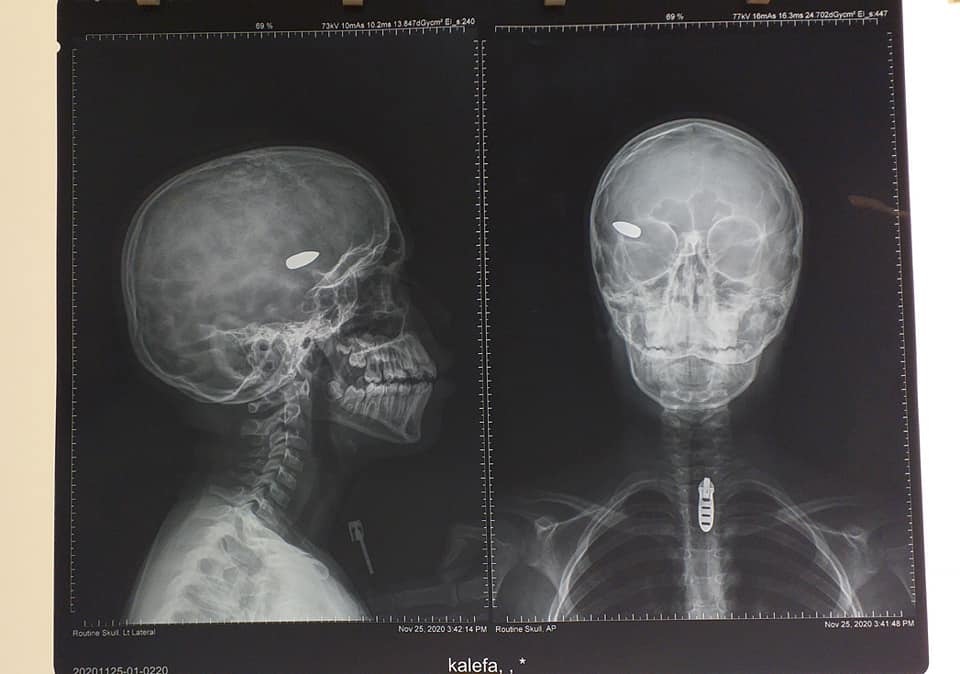

أجرى الفريق الطبي بمركز بنغازي الطبي، الجمعة عملية جراحية لدماغ طفل يبلغ من العمر 11 عامًا كانت قد اخترقت رأسه رصاصه عشوائية.

وأشار المركز، إلى أنه بعد إجراء الفحوصات والصور تبيّن أن الرصاصة مستقرة بقاع الجمجة وأجريت له العملية على يد جراح للمخ والأعصاب وتكللت بالنجاح.